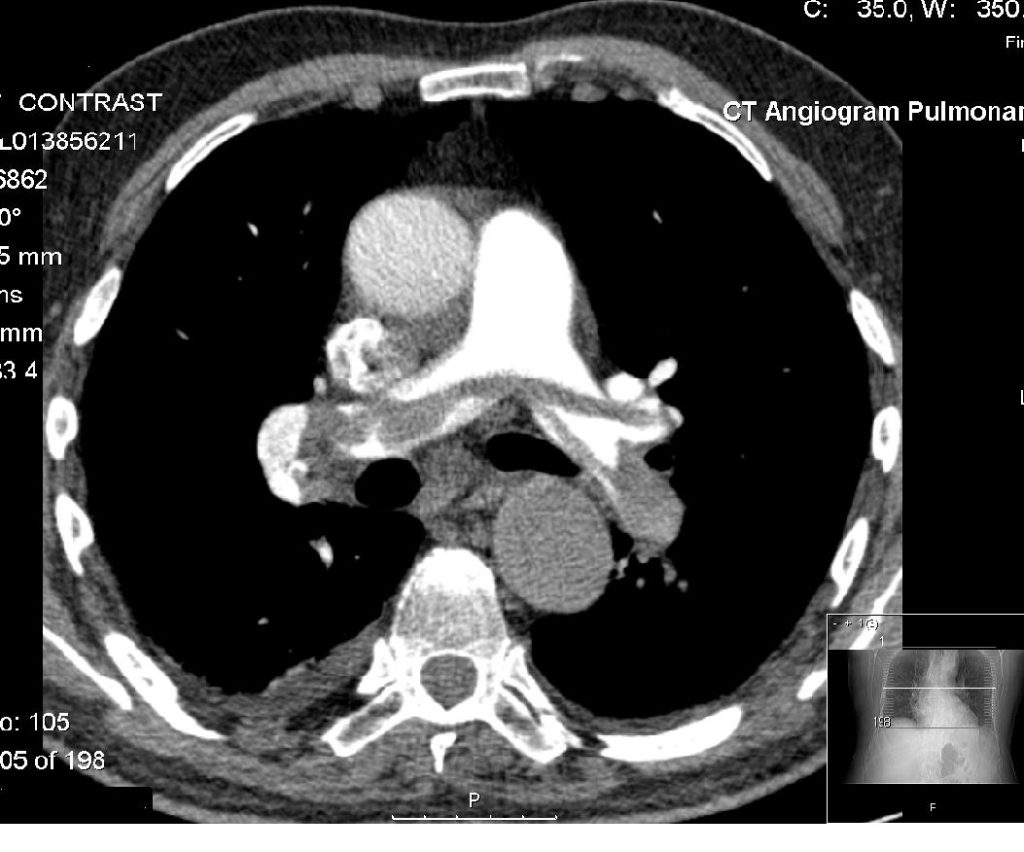

A CT angiogram is a test that checks for blockages and other problems in your arteries. It’s a CT scan with the added benefit of contrast dye. A healthcare provider injects the dye into a vein in your arm. The dye flows through your blood vessels and makes them look bright on the CT images. This means it’s easier to see blood flow and spot issues.

سی تی آنژیوگرافی آزمایشی است که انسداد و سایر مشکلات شریان های شما را بررسی می کند. این یک سی تی اسکن با مزایای اضافی رنگ کنتراست است. یک ارائه دهنده مراقبت های بهداشتی رنگ را به رگ بازوی شما تزریق می کند. رنگ در رگهای خونی شما جریان مییابد و آنها را در تصاویر CT روشن میکند. این بدان معنی است که دیدن جریان خون و تشخیص مشکلات آسان تر است